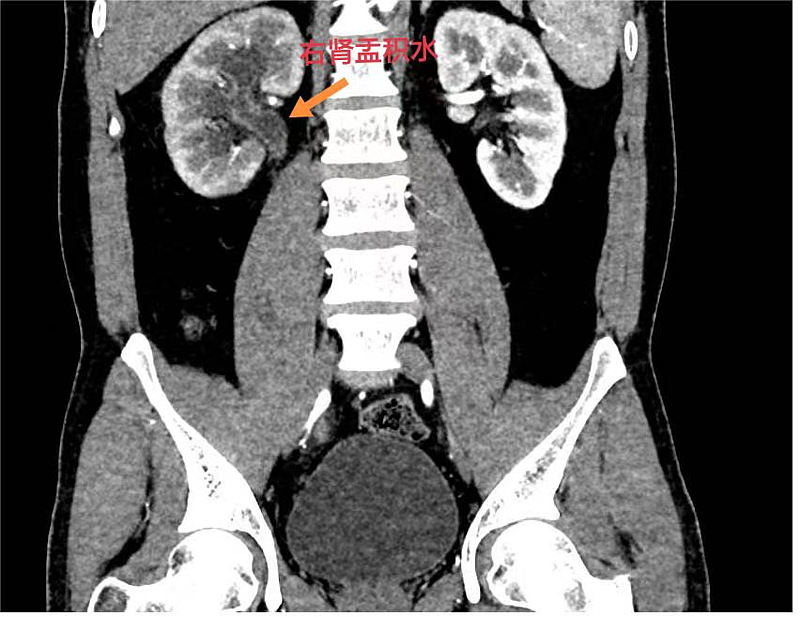

11岁的患者刘某,在入学体检时发现右肾积水,但平时并没有任何症状。泌尿外科完善CTU及逆行输尿管造影,明确诊断为右侧肾盂输尿管连接处狭窄。在明确告知患者家属病情并征得同意后,泌尿外科团队为患者实施了后腹腔镜下右侧肾盂成型术,仅需三个5mm的小切口就能完成手术,术后3天患者顺利出院。